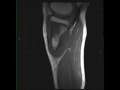

Periosteal Osteosarcoma, Tibia

21-year-old male with pain in the proximal left leg. There is an infiltrative T1 hypointense lesion circumferentially extending along the medial cortical margin of the proximal left tibia. The hypointense signal extends into the medullary cavity of the proximal tibia. The lesion is STIR hyperintense and avidly enhances. Imaging findings are compatible with a periosteal osteosarcoma. Periosteal osteosarcoma is the second most common type of surface osteosarcoma after the parosteal subtype. Periosteal osteosarcoma arise from the inner germinative layer of periosteum. Lesions tend to be diaphyseal with the femur and tibia most commonly affected. The lesion arises from the cortical margin with intramedullary extension being rare.